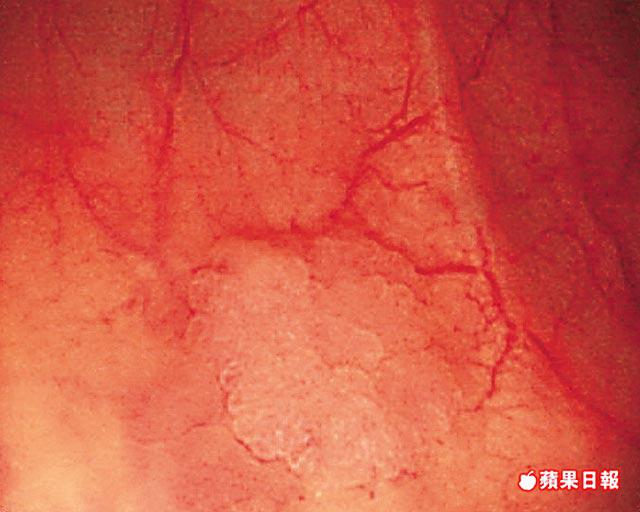

要提高大腸鏡尋找扁瘜肉的效率,梁偉強表示,需配合其他檢查方法,例如加入顯影技術,便可呈現出瘜肉附近的異常血管分佈,從而判別及切除扁瘜肉。不過,檢查準確度要視乎很多因素,例如非常扁平、細小或位於大腸彎位的扁瘜肉,容易因檢查速度過快而被遺漏。他指出一般進行大腸鏡檢查時間為入鏡10分鐘,出鏡6分鐘,加上仔細觀察及其他顯影技術,扁瘜肉便會原形畢露。